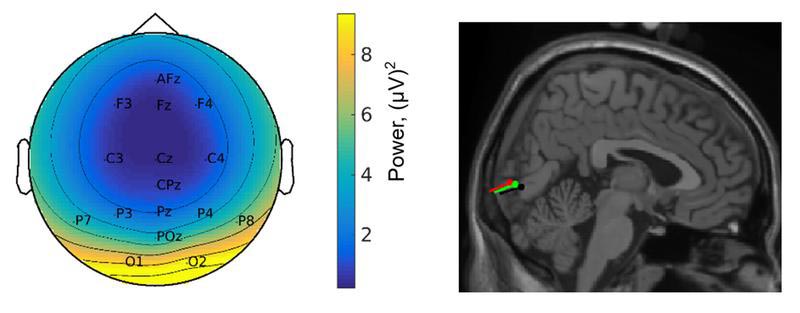

De proefpersonen kregen tijdens het onderzoek een kap op hun hoofd met elektroden, om hun hersenactiviteit te meten. Daarnaast hadden zij bewegingssensoren, videobrillen en een mobiel apparaat om de oogbewegingen vast te leggen. In een rugzak zat een laptop, die de EEG-data vastlegde. Dat kostte allemaal wel veel moeite, geeft Händel toe. Maar als je de waarnemingsstrategie van een mens bij natuurlijk gedrag wil begrijpen, dan moet je die moeite maar nemen. Het onderzoek naar de waarneming van de mens tijdens het bewegen, staat nog maar in de kinderschoenen.